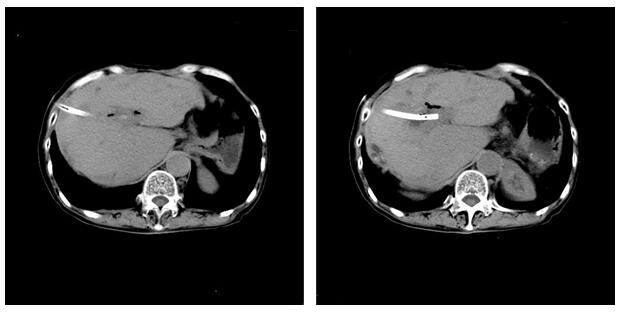

我院在PTCS传统做法的基础上加以改进,先行PTCD胆道引流控制胆管炎,术后1-2周,待患者炎症消退,一般情况恢复后,在全身麻醉下直接扩张瘘道至足够大小,放一个塑料吸管(保护性鞘管)到肝内胆管,先用直径3毫米的硬质胆道镜(不能拐弯)尽量取出细胆管内的结石,再用5毫米的纤维胆道软镜(可以拐弯)取角度刁钻的结石。这种做法缩短了治疗周期,创伤小、恢复快,减轻病人的痛苦。肚子上打了个5毫米的小洞,通过改进后的经皮经肝胆道镜取石PTCS手术,周某的肝内胆管结石被完全取尽(见图2)。患者没有再寒战、发烧、肚子痛,眼睛和皮肤黄疸也消退了,术后顺利康复出院。

图2患者术后CT检查。肝内胆管未见结石,肝内胆管有一直径约5毫米的引流管用于术后引流胆汁,引流管在出院前拔除。